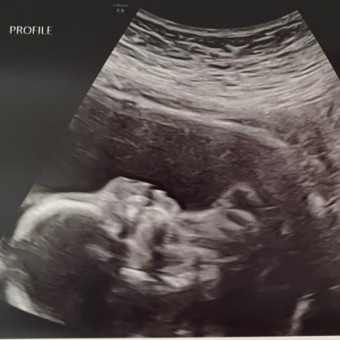

Hello everyone! Thank you for viewing our registry! ☺️ We are ready to welcome Madeline Jones Brewer in March 2026! 🩷

Pearhead "Love at First Sight" Sonogram Frame

babylist Icon

$12.99

target Icon

amazon Icon

from $9.99

I purchased this